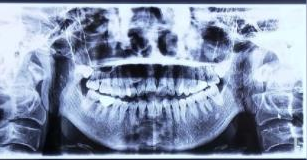

牙齒開合